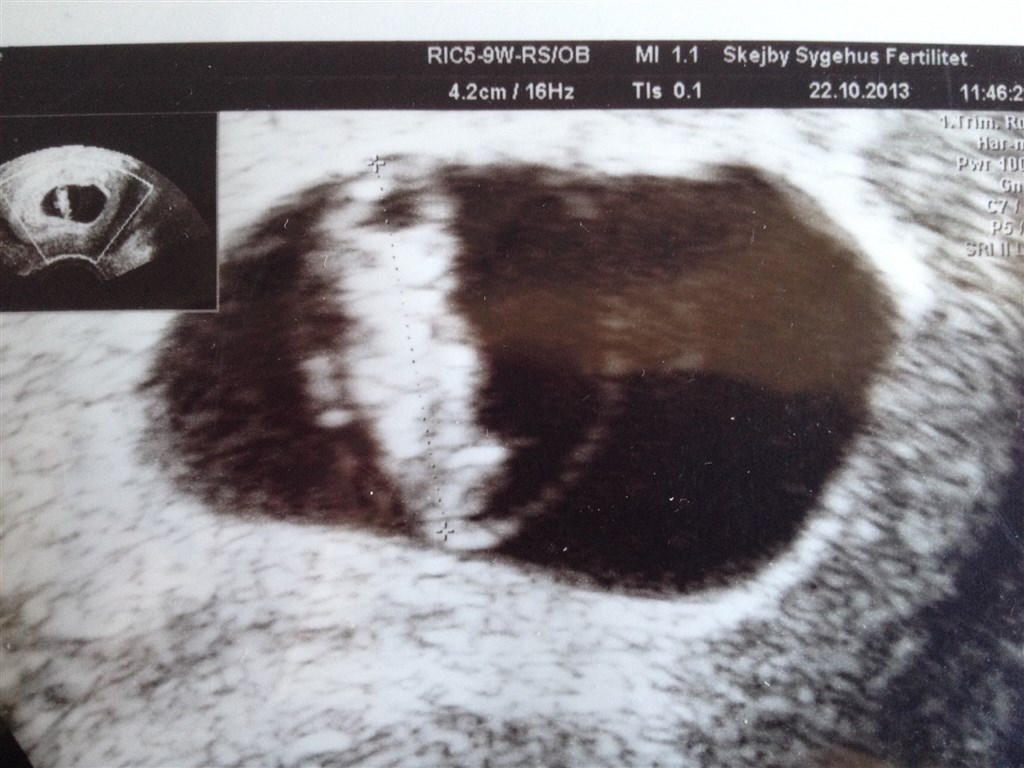

Jeg skal scannes imorgen for første gang. Er så spændt og nervøs på samme tid. Vi har termin samme dag! Fik man billeder med hjem og er scanningen indvendig?

Ja, det var en indvending scanning og jeg fik 2 fine billeder med uden beregning